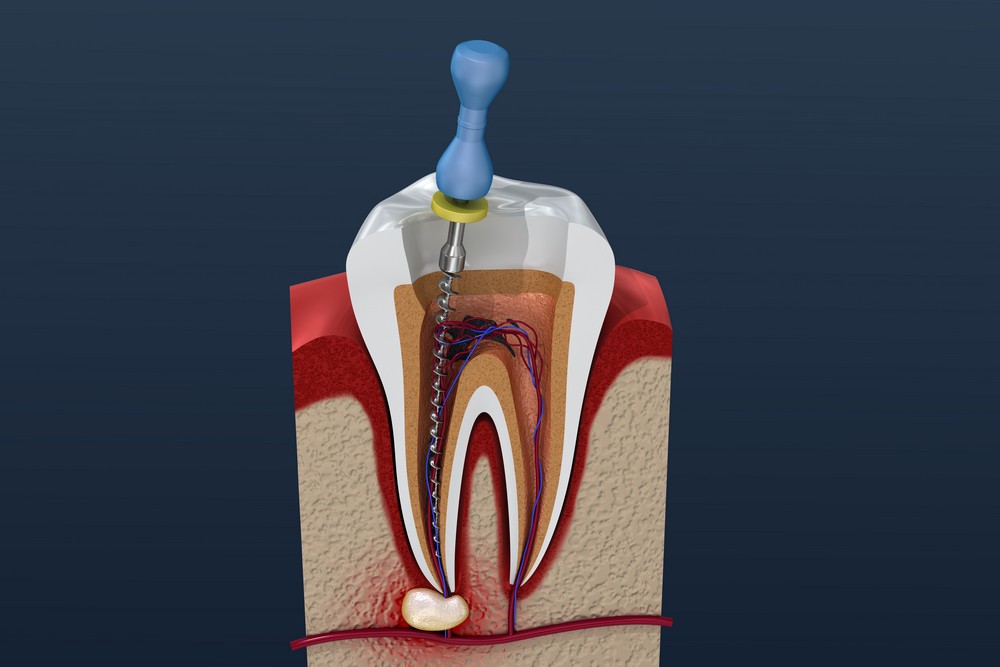

În linii mari, dintele uman poate fi împărţit în două părți: coroana și rădă-cina. Coroana este formată din smalț, dentină şi pulpă. Rădăcina dintelui este formată din canal radicular, cameră pulpară, parodonţiu, apex. Pulpa dentară, ţesutul moale de sub stratul de dentină, conține vase de sânge, nervi, țesut conjunctiv și are funcţie de nutriţie, dentinogenetică (depunere de dentină secundară sau terţiară), senzitivă şi defensivă (apărare). Dacă dintele este complet dezvoltat, va supraviețui fără pulpă, datorită hranei oferite de țesuturile din jur.

Tratamentul de canal este cea mai obişnuită procedură endodontică şi are drept scop vindecarea şi salvarea rădăcinii (rădăcinilor) dintelui, deci şi a dintelui în întregul său.

Este o procedură dentară în care dintele poate fi tratat prin îndepărtarea conţinutului camerei lui pulpare și umplerea acesteia cu un material de umplere adecvat. Tratamentul se aplică atunci când dintele nu mai pote fi umplut cu plombă (nu mai poate fi plombat) sau restaurat prin alte mijloace, din cauza faptul că infecţia pulpară produsă de bacteriile pătrunse prin caria dentară este avansată, cuprinzând ţesuturi, nervi, producând severe dureri acute şi abcese gingivale.

Tratamentul pe canalul radicular este ultima încercare de a salva dintele, al cărui nerv a fost distrus de infecţie, necrozat sau grav deteriorat, înainte de “capitulare”, adică de decizia finală de a scoate dintele, în lipsa oricărei alte soluţii posibile. Dacă tratamentul de canal (tratamentul endodontic) reuşeşte cu succes, toate focarele de infecţie din zona rădăcinii sunt eliminate, curăţarea completă a canalelor asigurând, în continuare, o viaţă lungă dintelui.

Tratamentul (terapia) de canal radicular este o procedură care aparţine specialităţii endodontice a stomatologiei, este un tratament endodontic, nume ce provine de la grecescul “endo”, adică “interior”, şi “odont”, adică “a avea dinţi (de un anumit tip)”. Este, deci, un tratament care se referă, practic, la tratarea interiorului dinţilor.

Tratamentul de canal se impune cu necesitate atunci când țesutul pulpar din interiorul canalului radicular se inflamează sau se infectează, afectând astfel alimentarea cu sânge a nervului – care este partea vitală a dintelui – şi a dintelui. Afecţiunea este cauzată de diverse motive, precum carii profunde şi avansate, fisurile sau ciobirile dinţilor, dar şi de efectuarea prea deasă a procedurilor dentare.